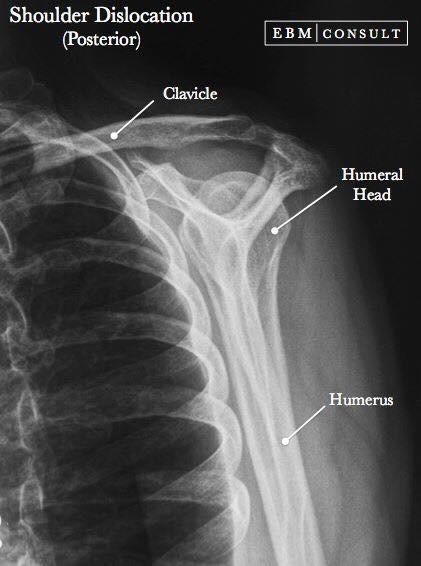

Las radiografías, generalmente llamadas rayos X, producen imágenes como sombras de huesos y ciertos órganos y tejidos. Las radiografías son muy buenas para detectar problemas óseos. Pueden mostrar algunos órganos y tejidos blandos; sin embargo, la MRI y la CT suelen crear mejores imágenes de los mismos. Aun así, las radiografías son rápidas, fáciles de obtener y menos costosas que los otros estudios, por lo que se pueden usar para obtener información rápidamente.

Un tubo especial dentro de la máquina de rayos X emite un haz de radiación controlada. Los tejidos del cuerpo absorben o bloquean la radiación en diferentes grados. Los tejidos densos como los huesos bloquean la mayor parte de la radiación, pero los tejidos blandos, como la grasa o los músculos, bloquean menos radiación. Después de pasar por el cuerpo, el haz alcanza una pieza de un fragmento de película o un detector especial. Los tejidos que bloquean altas cantidades de radiación, como los huesos, aparecen como áreas blancas en un fondo negro. Los tejidos blandos bloquean menos radiación y aparecen en tonos de gris. Los órganos que contienen principalmente aire (como los pulmones) aparecen en negro. Los tumores son por lo general más densos que el tejido que los rodea, por lo que suelen verse en tonos grises más claros.